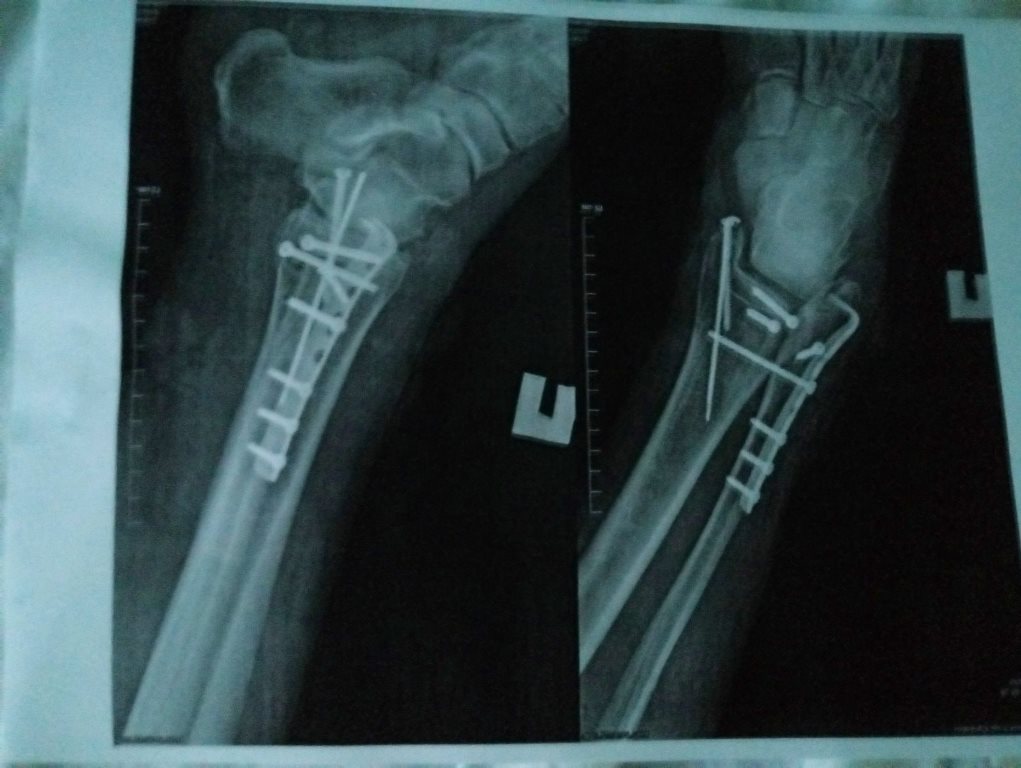

"Сначала они били по кузову автомобиля Skoda Fabia, в котором находились 3 пассажира-пенсионера, мужчины и одна женщина. После этого одному из пассажиров Skoda Fabia водитель автомобиля MG 5 нанес несколько ударов битой по грудной клетке (результат-ушиб грудной клетки), а его напарник ногами избил второго самого физически слабого 65-ти летнего пассажира Skoda Fabia (результат - перелом ноги в трех местах)", - написал Барбашин.